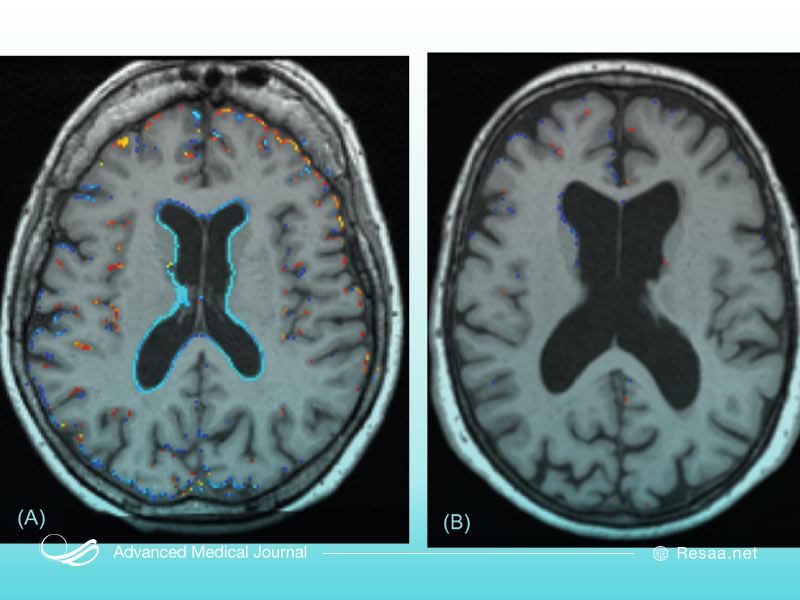

تشخیص آتروفی مغز یا کاهش سلول

به طور معمول، آتروفی مغزی با آزمایشات تصویربرداری مغز شناسایی میشود. این آزمایشات میتوانند شامل توموگرافی کامپیوتری (CT)، تصویربرداری با تشدید مغناطیسی (MRI)، توموگرافی انتشار پوزیترون (PET) یا توموگرافی رایانه ای تک فوتونی (SPECT) باشد.

در صورت بروز علائمی مانند ضعف، بی حسی، بینایی، از دست دادن یا تغییر شخصیت، ممکن است تیم پزشکی CT یا MRI مغزی را تجویز کنند. به طور کل، PET و SPECT اغلب به جای اهداف بالینی برای اهداف تحقیقاتی انجام میشوند. این آزمایشات ممکن است آتروفی مغزی عمومی یا مناطقی از آتروفی مغزی کانونی را شناسایی کنند. گاهی اوقات وقتی مناطقی از آتروفی در معاینه تصویربرداری از مغز ذکر شده است، میتواند به تشخیص وضعیت پزشکی به شرح زیر کمک کند: